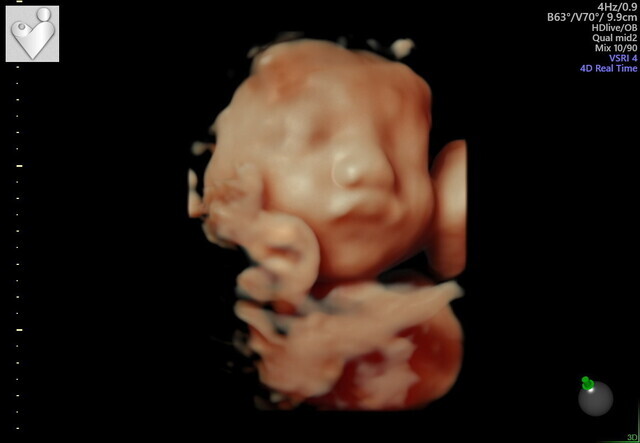

29週0日(29w0d・男の子)|haorinさん(29歳)

エコー写真撮影時のエピソード:

妊娠を通して悪阻は全くなく、とても楽しいマタニティライフでした。エコー写真でこんなにはっきり顔が見えて、愛おしさがさらに増しました。この時期はまだ産休にも入っていなかったので、周りの人に支えられながら働いていました。出産後、見比べても面影があります。